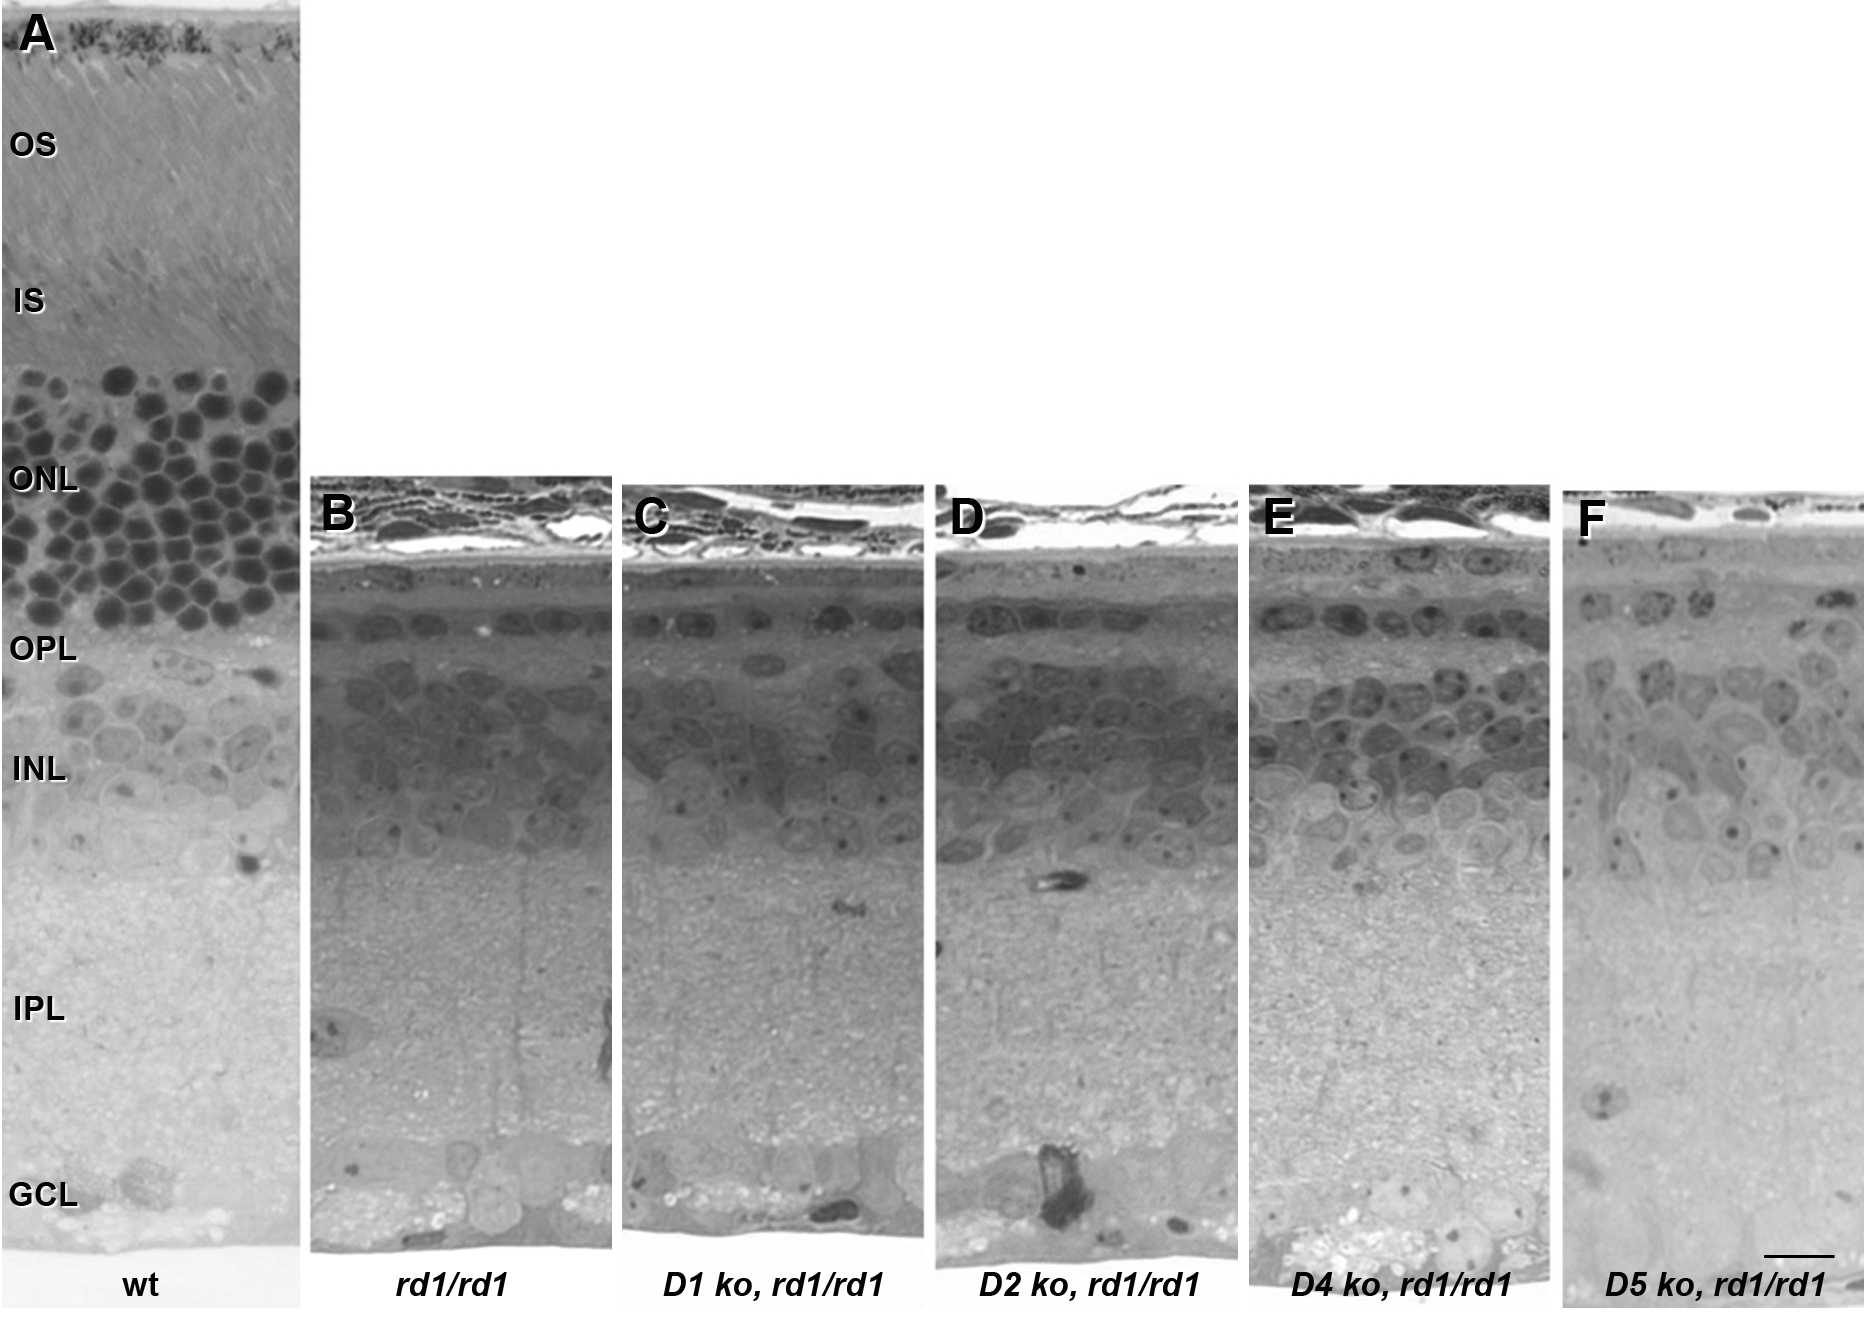

Figure 1. Dopamine receptor deletion does

not alter photoreceptor cell survival in rd1 retinas in vivo.

Retinas from wild-type (A), rd1/rd1 (B), D1−/−,

rd1/rd1 (C), D2−/−, rd1/rd1 (D), D4−/−,

rd1/rd1 (E), and D5−/−, rd1/rd1 (F)

mice

were harvested at postnatal day 21. The ONL of rd1/rd1

retinas was reduced to a monolayer of photoreceptors, regardless of DR

genotype. Abbreviations: outer segments (OS); inner segments (IS);

outer nuclear layer (ONL); outer plexiform layer (OPL); inner nuclear

layer (INL); inner plexiform layer (IPL); ganglion cell layer (GCL).

The scale bar represents 10 μm.